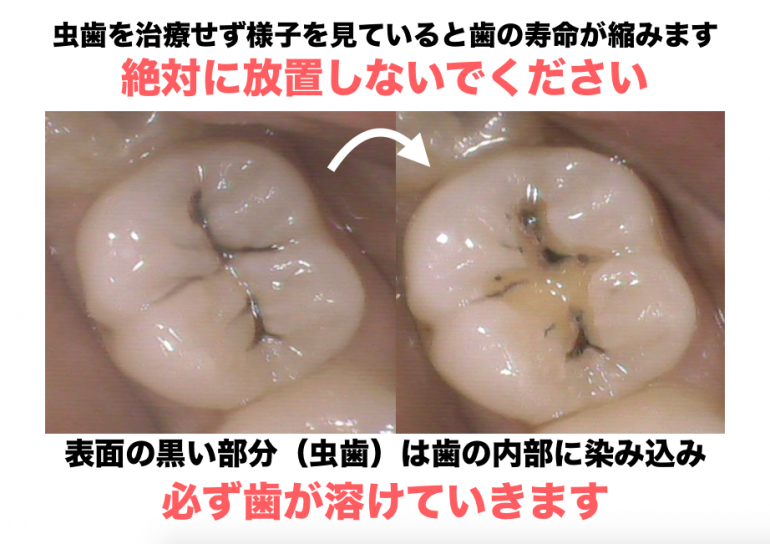

Q;なぜ小さい虫歯でも治した方がいいの?

A;一度虫歯になると回復することがなく、様子を見ていると痛みもなく歯の内部までゆっくり溶けていくため、虫歯と診断を受けたら早急に治す必要があります

虫歯は様子を見ていると必ず進行します

虫歯は歯が溶ける病気であり、一度溶けた歯は絶対に回復しません

歯科医師により小さい虫歯は様子を見て、天然歯を残そうとしますが、回復しない虫歯を様子を見ていて虫歯が進行すれば、天然歯は徐々に溶けてなくなります

つまり虫歯を様子を見るということは天然歯の寿命が縮むことになります

早期に治せば、虫歯になっている部分だけを取り除き天然歯の健康な部分を残すことができます

しかし、虫歯を様子を見ていることにより虫歯で内部が溶けてしまえば、天然歯の健康な部分まで余分に削り取り歯を修復するため歯の歯の寿命は縮みます

そのため、虫歯は早期発見・早期治療が必要です